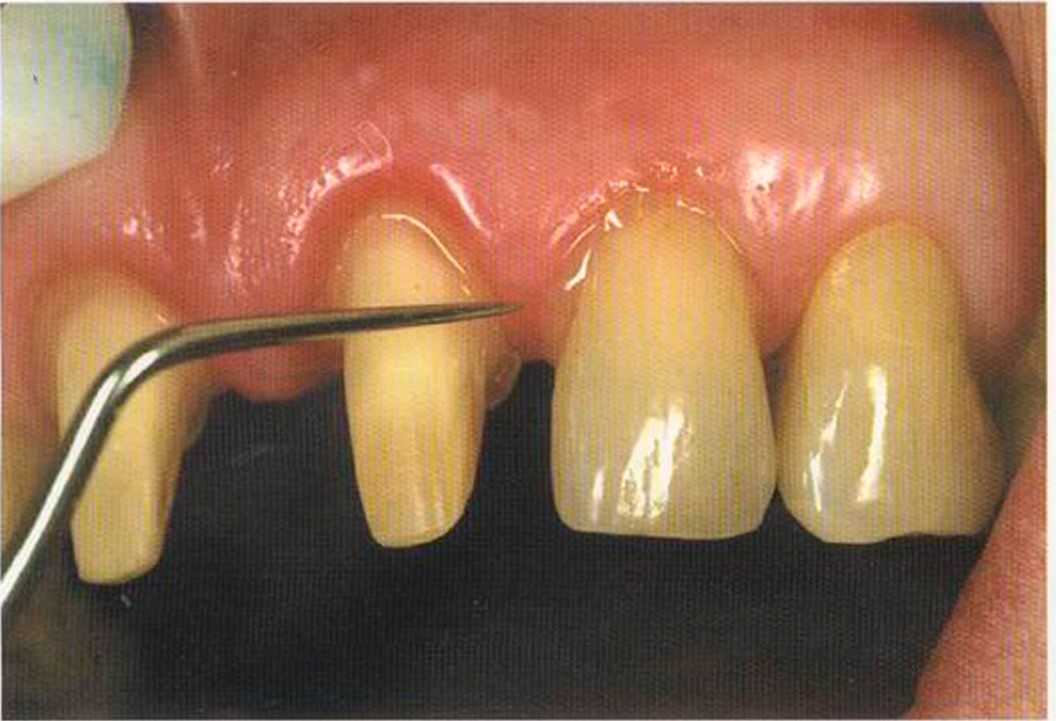

Фото сверху и слева: отличный результат препарирования зубов с уже уложенными нитями для снятия оттиска.

Препарирование, проводимое доктором Риссе, оценивается как очень сложное. Режущие края центральных резцов сильно дивергируют, что создает неудобство при формировании хорошего уступа.

Из-за сильной протрузии центральных резцов на них всегда падает итого света, и они кажутся очень большими. Чтобы смягчить этот эффект, мы выбрали более темный цвет для реставрации.